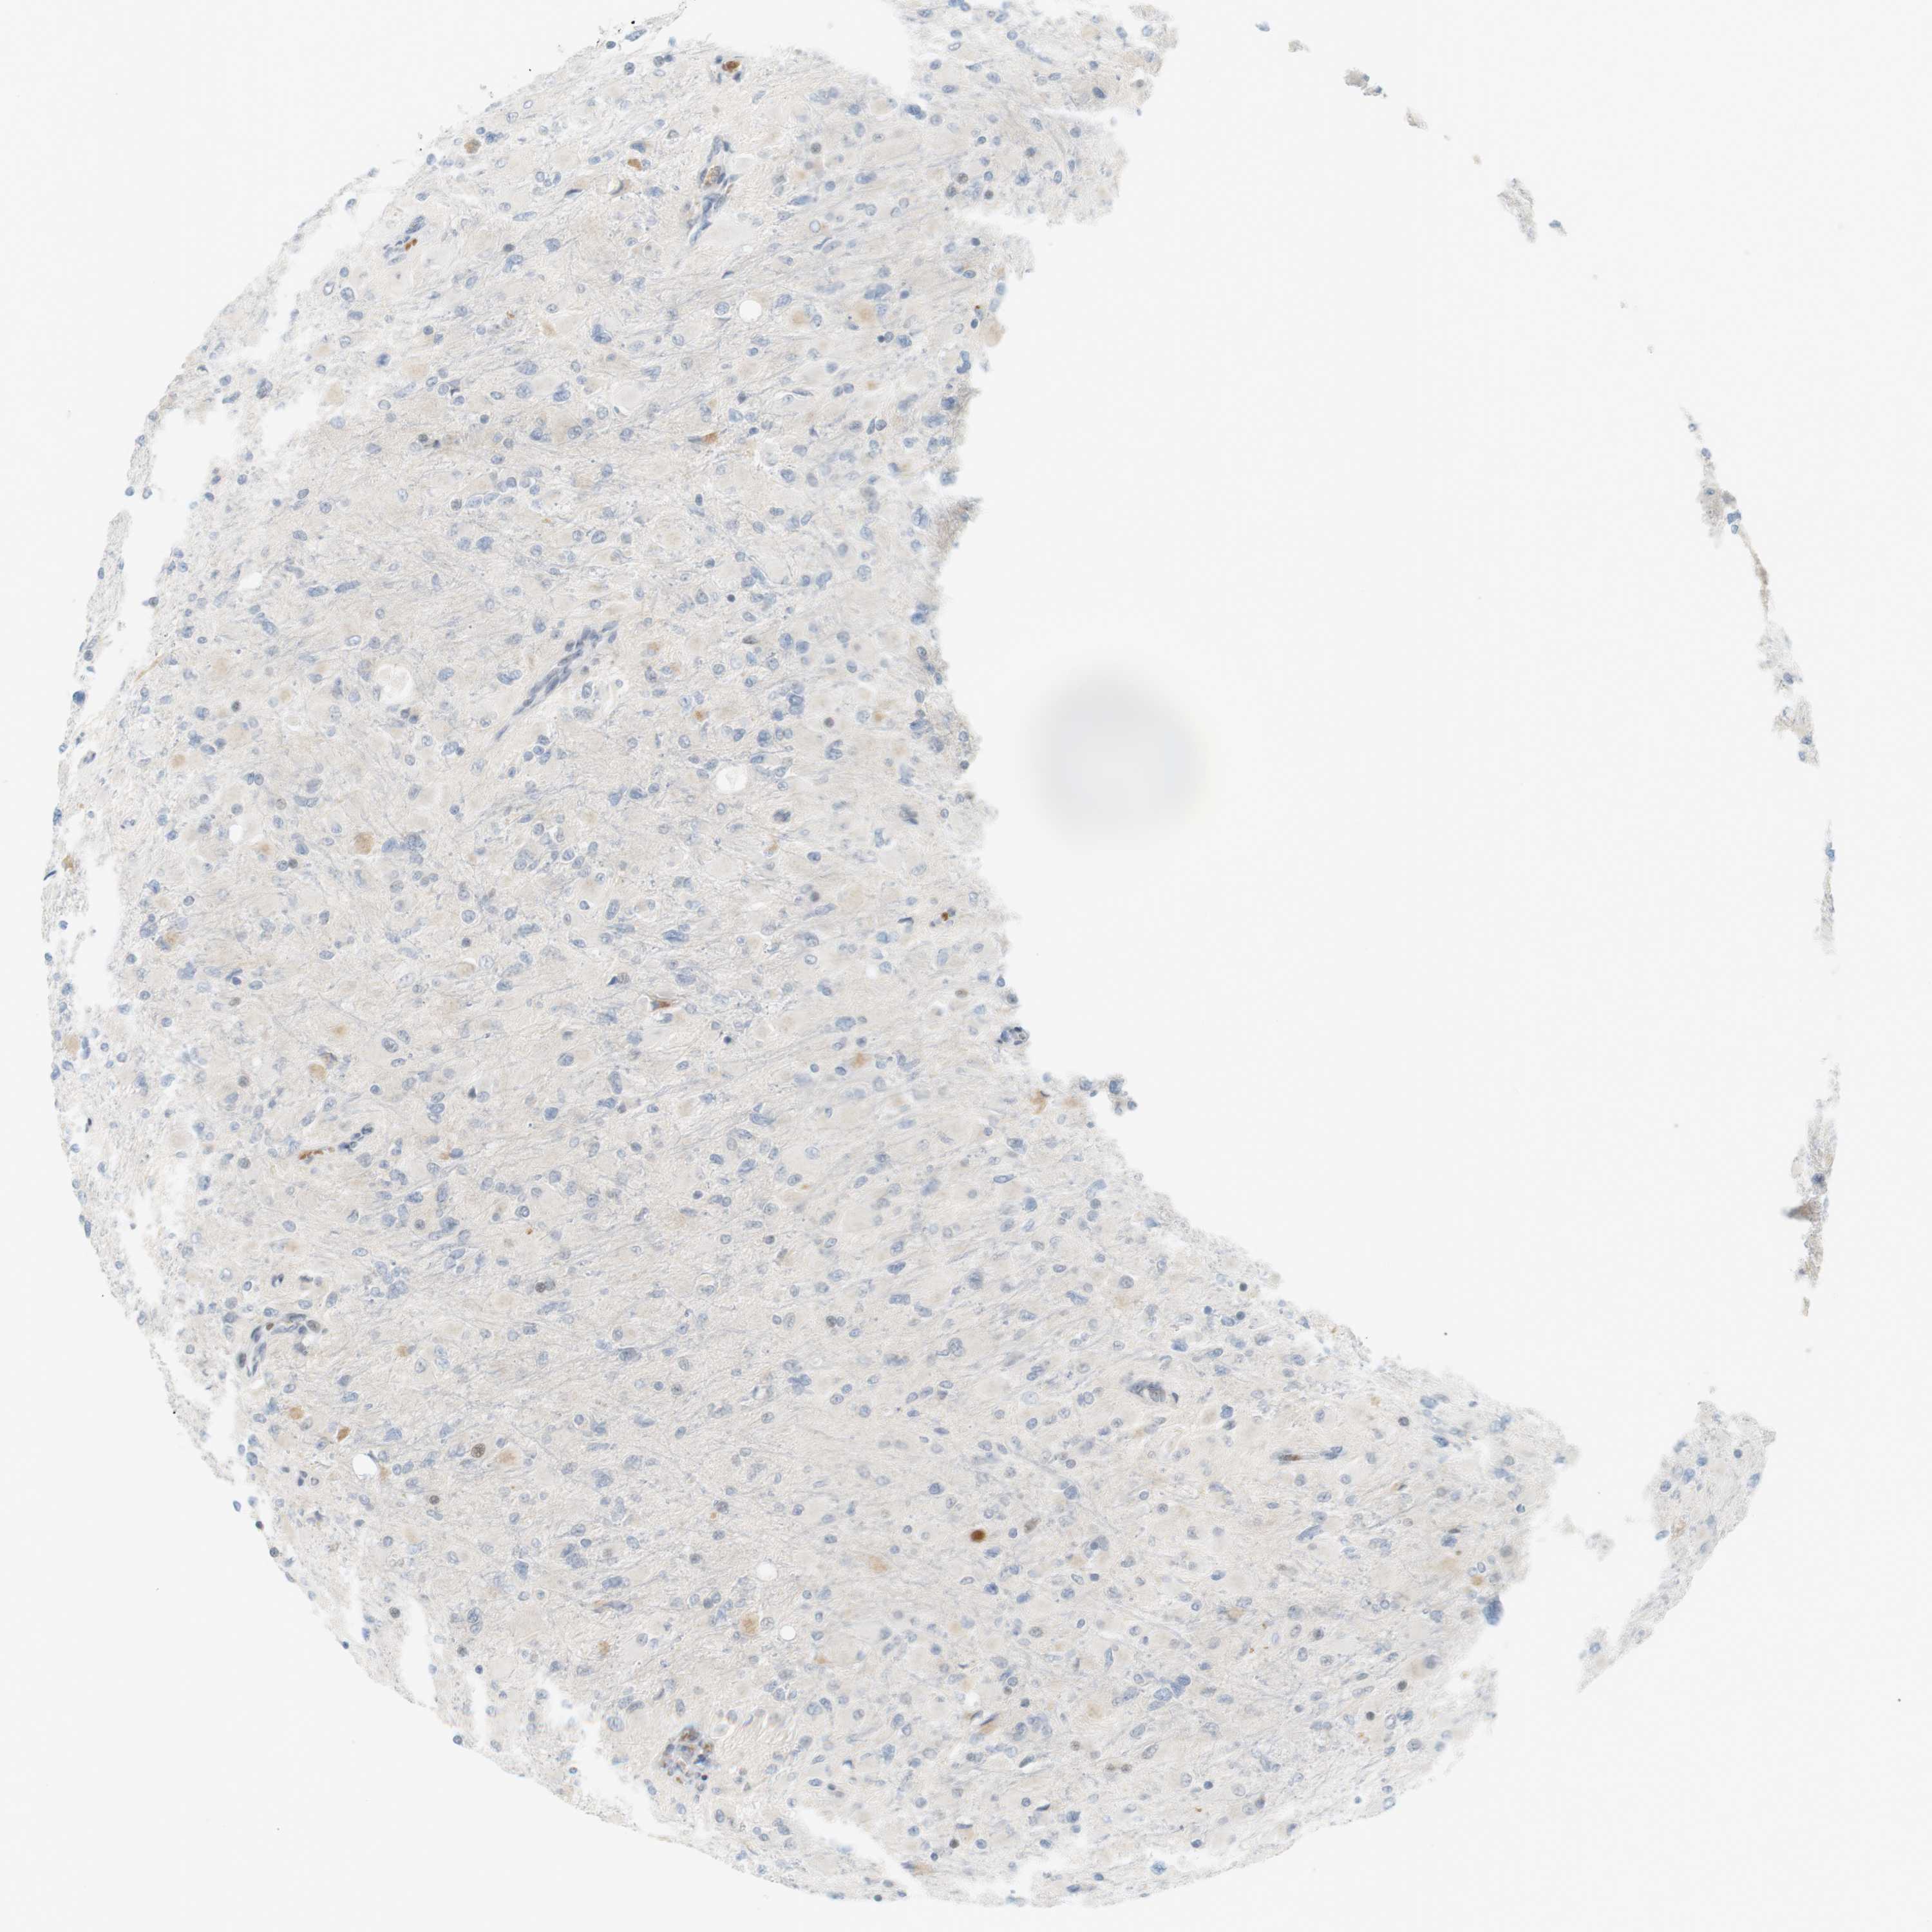

GLIOMA - Protein expressioni

A mouse-over function shows sample information and annotation data. Click on an image to view it in a full screen mode. Samples can be filtered based on level of antibody staining by selecting one or several of the following categories: high, medium, low and not detected. The assay and annotation is described here.

Note that samples used for immunohistochemistry by the Human Protein Atlas do not correspond to samples in the TCGA dataset.

Antibody stainingi

Antibody staining in the annotated cell types in the current human tissue is reported as not detected, low, medium, or high, based on conventional immunohistochemistry profiling in selected tissues. This score is based on the combination of the staining intensity and fraction of stained cells.

Each image is clickable and will lead to virtual microscopy that enables deeper exploration of all samples and also displays staining intensity scores, fraction scores and subcellular localization as well as patient and tissue information for each sample.

Antibody HPA001232

Antibody CAB015397

Staining

High

Medium

Low

Not detected

Intensity

Strong

Moderate

Weak

Negative

Quantity

>75%

75%-25%

<25%

None

Location

Nuclear

Cytoplasmic/membranous

Cytoplasmic/membranous,nuclear

Glioma, malignant, High grade

Glioma, malignant, Low grade